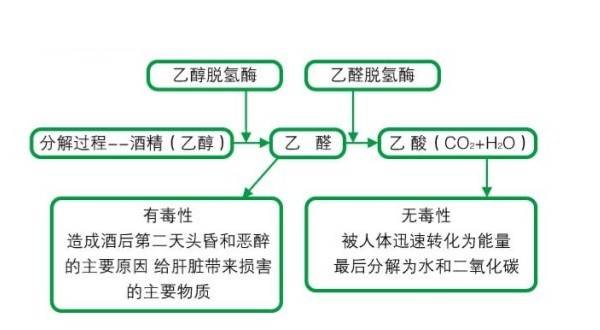

你的代谢会影响到减脂的效果,如何提升代谢,让减脂更高效当我们为了身材而付出努力之时,如何变瘦可能是我们首先想到的事情,所以如何有效减脂就会成为我们非常关注的话题,但是,减脂并没有我们想象得那么简单,因为减脂是一个需要长期坚持的事情,而非一蹴而就的过程,它需要合理的饮食搭配、规律的运动以及一个高效运转的代谢系统。所...

代谢下降会让减脂困难,如何提高代谢水平,让减脂变容易?我们代谢也会因为年龄等因素而下降,也正是因为如此,很多中年朋友都在面临着发福变胖的问题,即使他们在年轻之时怎么吃也不胖也是一样;即... 当代谢的下降而减少的消耗抵消在饮食上减少的摄入之时,体重就不会再下降了,这就是为什么在减脂过程中,我们的体重会经历一个由快到慢然...

人到中年易发福,如何提升代谢水平,保持纤细身材?如何在中年以后保持纤细的身材呢?这还要从中年发福的原因说起。第一:为会人到中年会发福变胖?人到中年为何会发福变胖?这一现象背后隐藏着多重原因,既有生理层面的变化,也有生活方式上和改变。1.生理因素的变化从生理角度来看,随着年龄的增长,人体的新陈代谢逐渐放缓。中年...